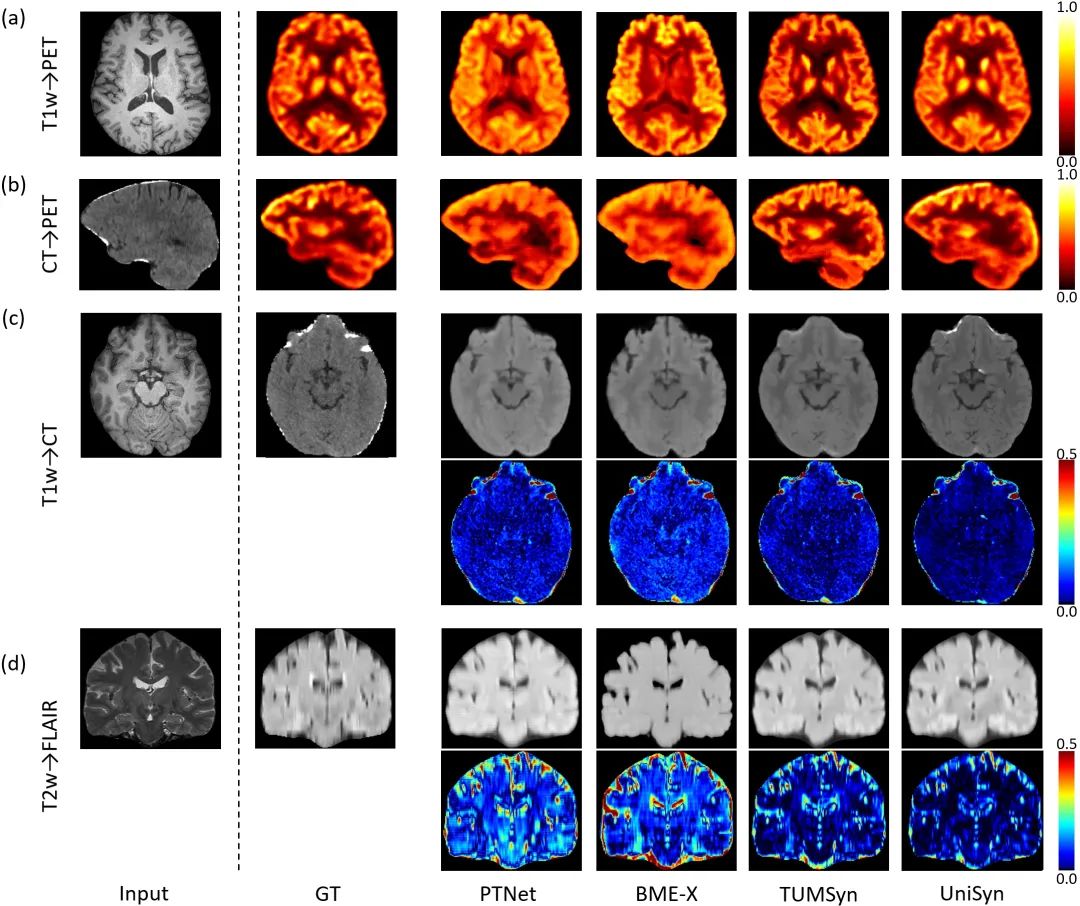

多模态脑影像(如MRI、CT 和 PET)通过提供互补的结构与功能信息,极大促进了人类对认知机制与神经系统疾病的认识。现有的跨模态影像合成方法大多针对特定任务或模态设计,缺乏统一性,在面对复杂多变的真实临床影像数据时,往往表现出性能下降和泛化能力不足的局限。沈定刚教授课题组博士后王誉霖等开发了一个通用的MRI/CT/PET跨模态图像生成基础模型UniSyn,可基于任意可用模态影像及其成像元数据,合成具备指定采集参数的目标模态影像。在多中心脑影像数据集上的大量实验证明,UniSyn 在合成影像的量化准确性和临床相关性方面均优于现有主流方法,能够针对不同临床与科研需求,灵活生成缺失的影像序列,为多模态脑影像智能补全及辅助诊断提供了可靠的新工具。

论文题目:Unisyn: A Generative Foundation Model for Universal Medical Image Synthesis across MRI, CT and PET